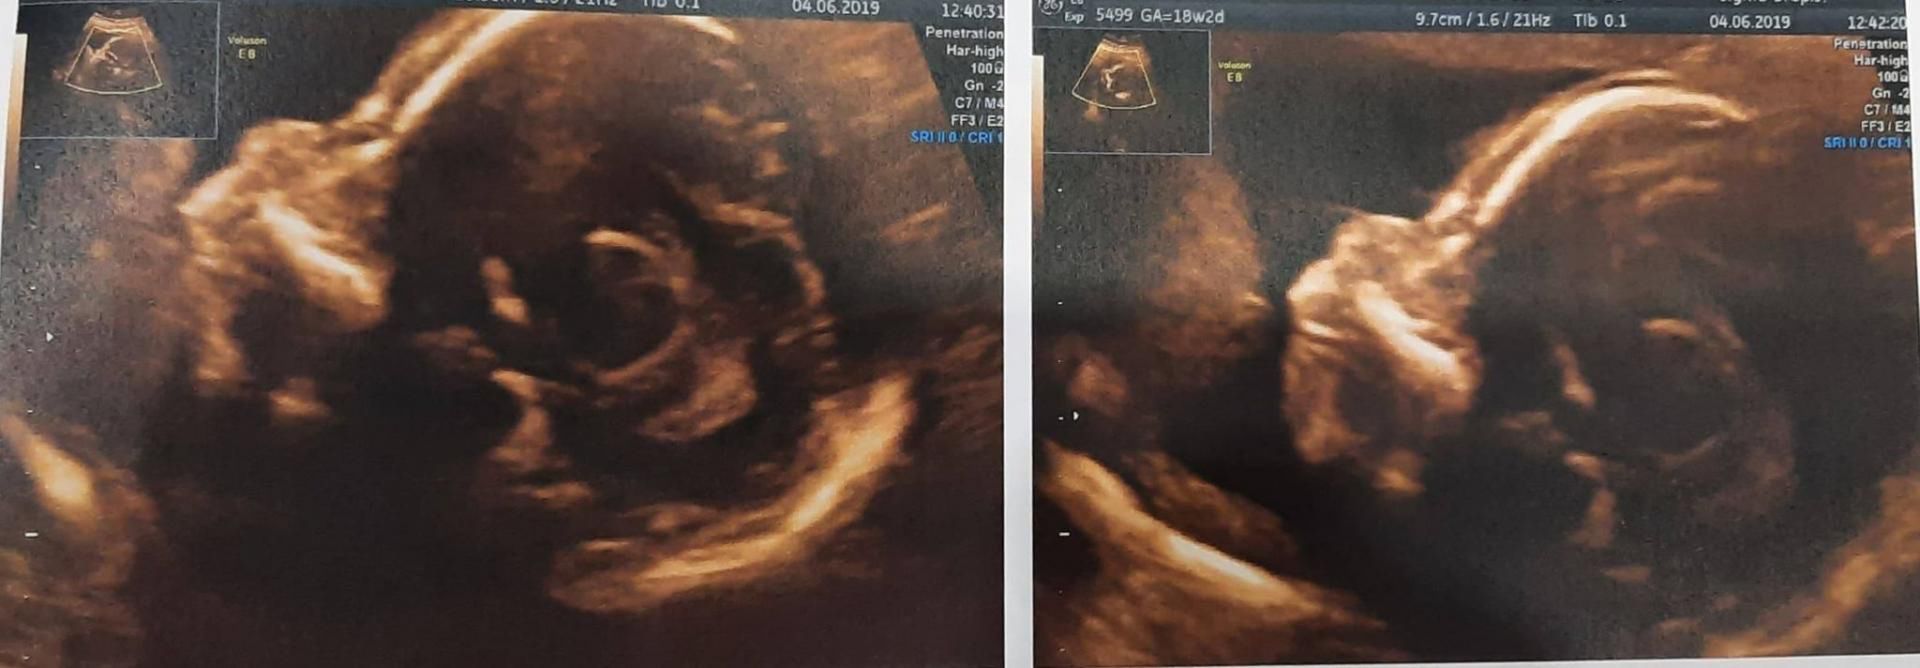

- Nie spodziewałam się, że usłyszymy coś takiego! “Serduszko bije pięknie, przezierność karku wynosi 2.0. Ogólnie anatomia płodu bez zastrzeżeń, ale martwi mnie kość nosowa… Niech pani spojrzy. Nie ma jej”. Tak powiedział lekarz - wspomina 30-letnia kobieta w rozmowie z WP parenting.

Każde kolejne badania wykazywało brak kości nosowej u dziecka

Każde kolejne badania wykazywało brak kości nosowej u dziecka © Materiały własne

Taki wynik nie oznacza braku wykształconego nosa, ale to, że kość nosowa jest słabo lub wcale niewidoczna. Specjalista dodał, że choć brak kości nosowej jest bardzo ważnym markerem m.in. zespołu Downa, to nie musi świadczyć o wadzie genetycznej. Zdarza się, że pojawia się ona później (z czasem uwapnienie kości może się poprawić). Statystyki mówią, że na tym etapie kość nosowa nie występuje u 80 proc. płodów z zespołem Downa i u 1 proc. płodów bez wady. Doris przyznaje, że nie pamięta dalszej części rozmowy z lekarzem, ponieważ była w szoku. W myślach pytała samą siebie: "Jak to możliwe?!".

A jednak w 18. tygodniu ciąży Doris poszła na badanie USG z nadzieją, że kość nosowa u córki będzie widoczna. Okazało się, że sytuacja nie uległa zmianie.

- Byłam bardzo zdziwiona, ponieważ wszystkie parametry były dobre, moja dziewczynka rosła w szybkim tempie, ale nadal nie było kości nosowej. Bałam się strasznie - mówi.